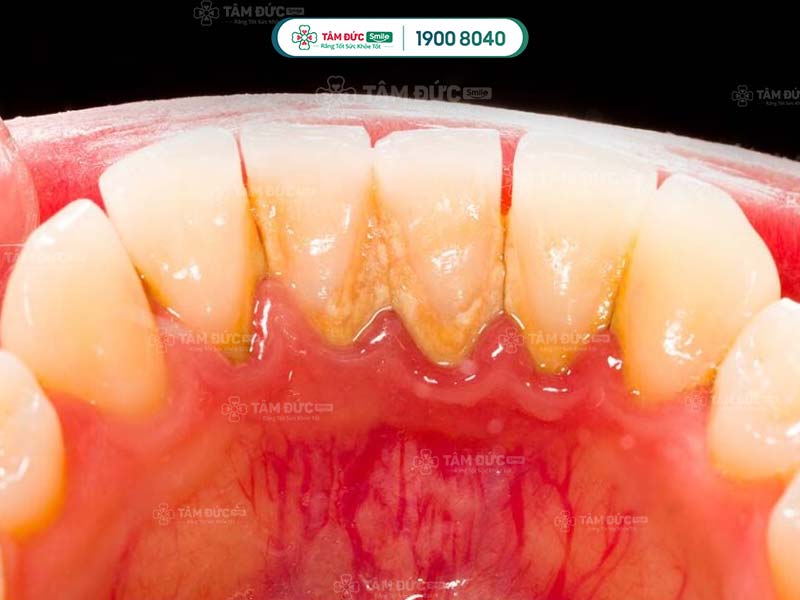

Cao răng cần được làm sạch triệt để bằng các dụng cụ chuyên dụng. Trong xuyên suốt quy trình cạo cao răng, Quý khách có thể bị ê buốt nhẹ.

Nếu cao răng nằm sâu trong chân răng, thao tác cạo cao răng có thể gây chảy máu. Vì vậy, Quý khách cần nhờ đến sự hỗ trợ của bác sĩ giỏi tay nghề để giảm thiểu rủi ro này.

cạo cao răng trả lại vẻ đẹp sáng bóng cho răng

Cạo cao răng để răng luôn sáng bóng và chắc khoẻ